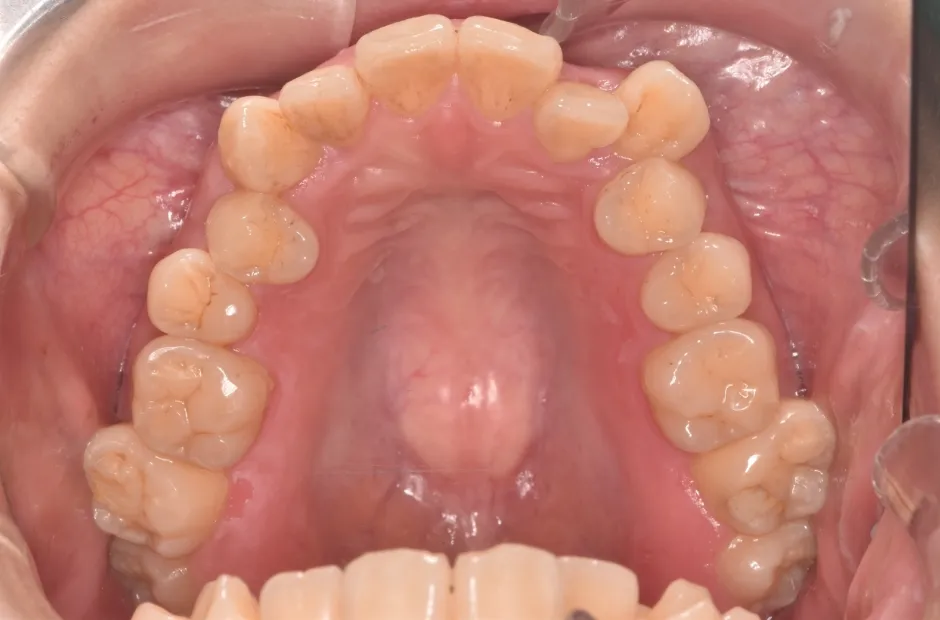

叢生

| 診断名・主訴 | 叢生 |

|---|---|

| 年齢・性別 | 43歳・女性 |

| 治療期間・回数 | 2年7か月 27回 |

| 治療に用いた主な装置 | 舌側矯正 |

| 抜歯部位 | 両顎4,4 |

| 治療費 | 100万円(税抜) |

| リスク・副作用 | 装置による違和感・疼痛・歯肉退縮・歯根吸収・虫歯のリスクなど |

治療前